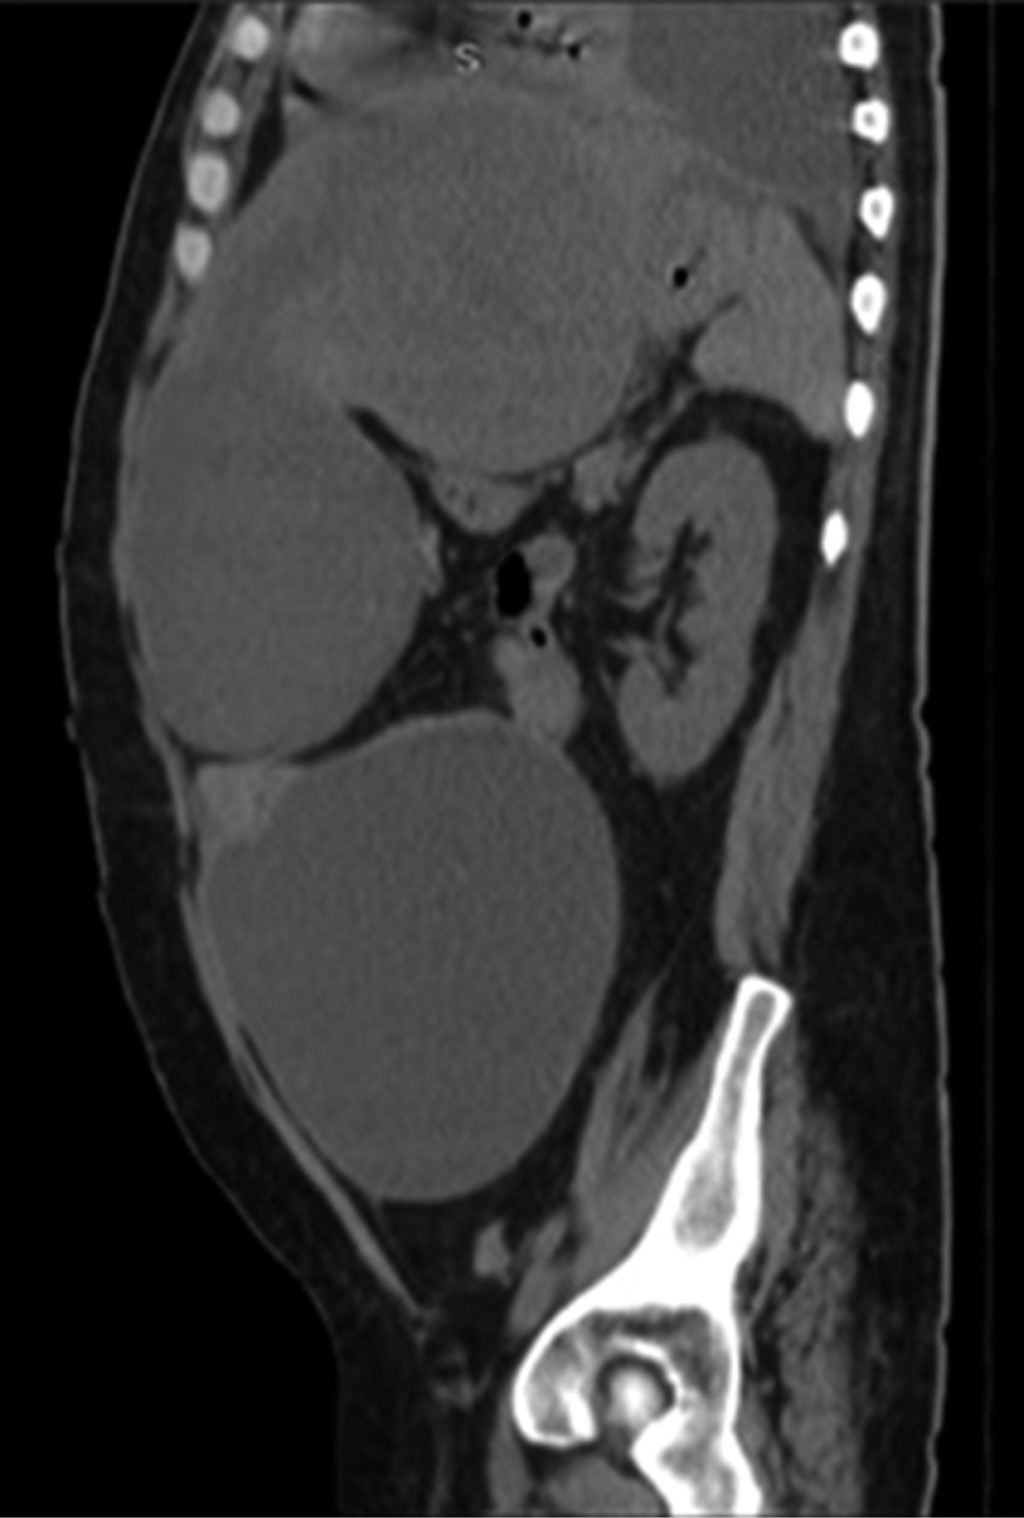

Se realizó una radiografía anteroposterior (AP) de tórax, en la cual se visualizó un derrame pleural izquierdo que cubría más de 50%. La tomografía computarizada mostró una importante cantidad de líquido en el espacio pleural izquierdo que condicionó una atelectasia pasiva del lóbulo inferior (Figura 1); el hígado se encontró con densidad heterogénea con incremento del lóbulo hepático izquierdo secundario a la presencia de una lesión heterogénea hipodensa con bordes lobulados, que muestra un reforzamiento periférico y de algunos septos internos, la cual abarca los segmentos II, III, IVa y IVb midiendo aproximadamente 20 × 14.5 × 12.5 cm (Figura 2), condicionando desplazamiento posterior y compresión del estómago y del páncreas y desplazamiento caudal de las asas intestinales (Figuras 3 y 4). En el polo inferior del lóbulo hepático derecho adyacente al segmento IV se identifica una lesión de aspecto quístico homogéneo con reforzamiento periférico tras la administración de contraste intravenoso, midiendo en sus ejes mayores 25 × 27 × 13 cm. Como manejo inicial se le colocó una sonda Foley y sonda nasogástrica presentando gasto de características gástricas (30 ml). Se colocó un catéter central, verificado por radiografía. Se solicitaron estudios de imagen. Se le indicó ayuno, se inició fluidoterapia, antibioticoterapia con ceftriaxona y metronidazol, manejo del dolor, control glucémico y protector gástrico. Al visualizar la imagen del derrame pleural izquierdo, se decide realizar una toracocentesis, obteniendo exudado espeso de aspecto "chocolatoso". Al momento de contar con la tomografía se inicia tratamiento quirúrgico urgente.

Figura 2